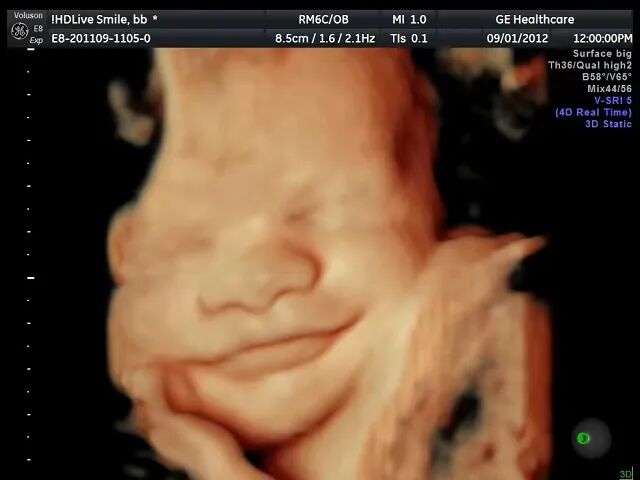

三维彩超

(看镜头,笑一个)

三维彩超是在二维超声的基础上,利用计算机再处理技术达到立体模式重建的超声诊断技术,能看到胎儿的立体图形。